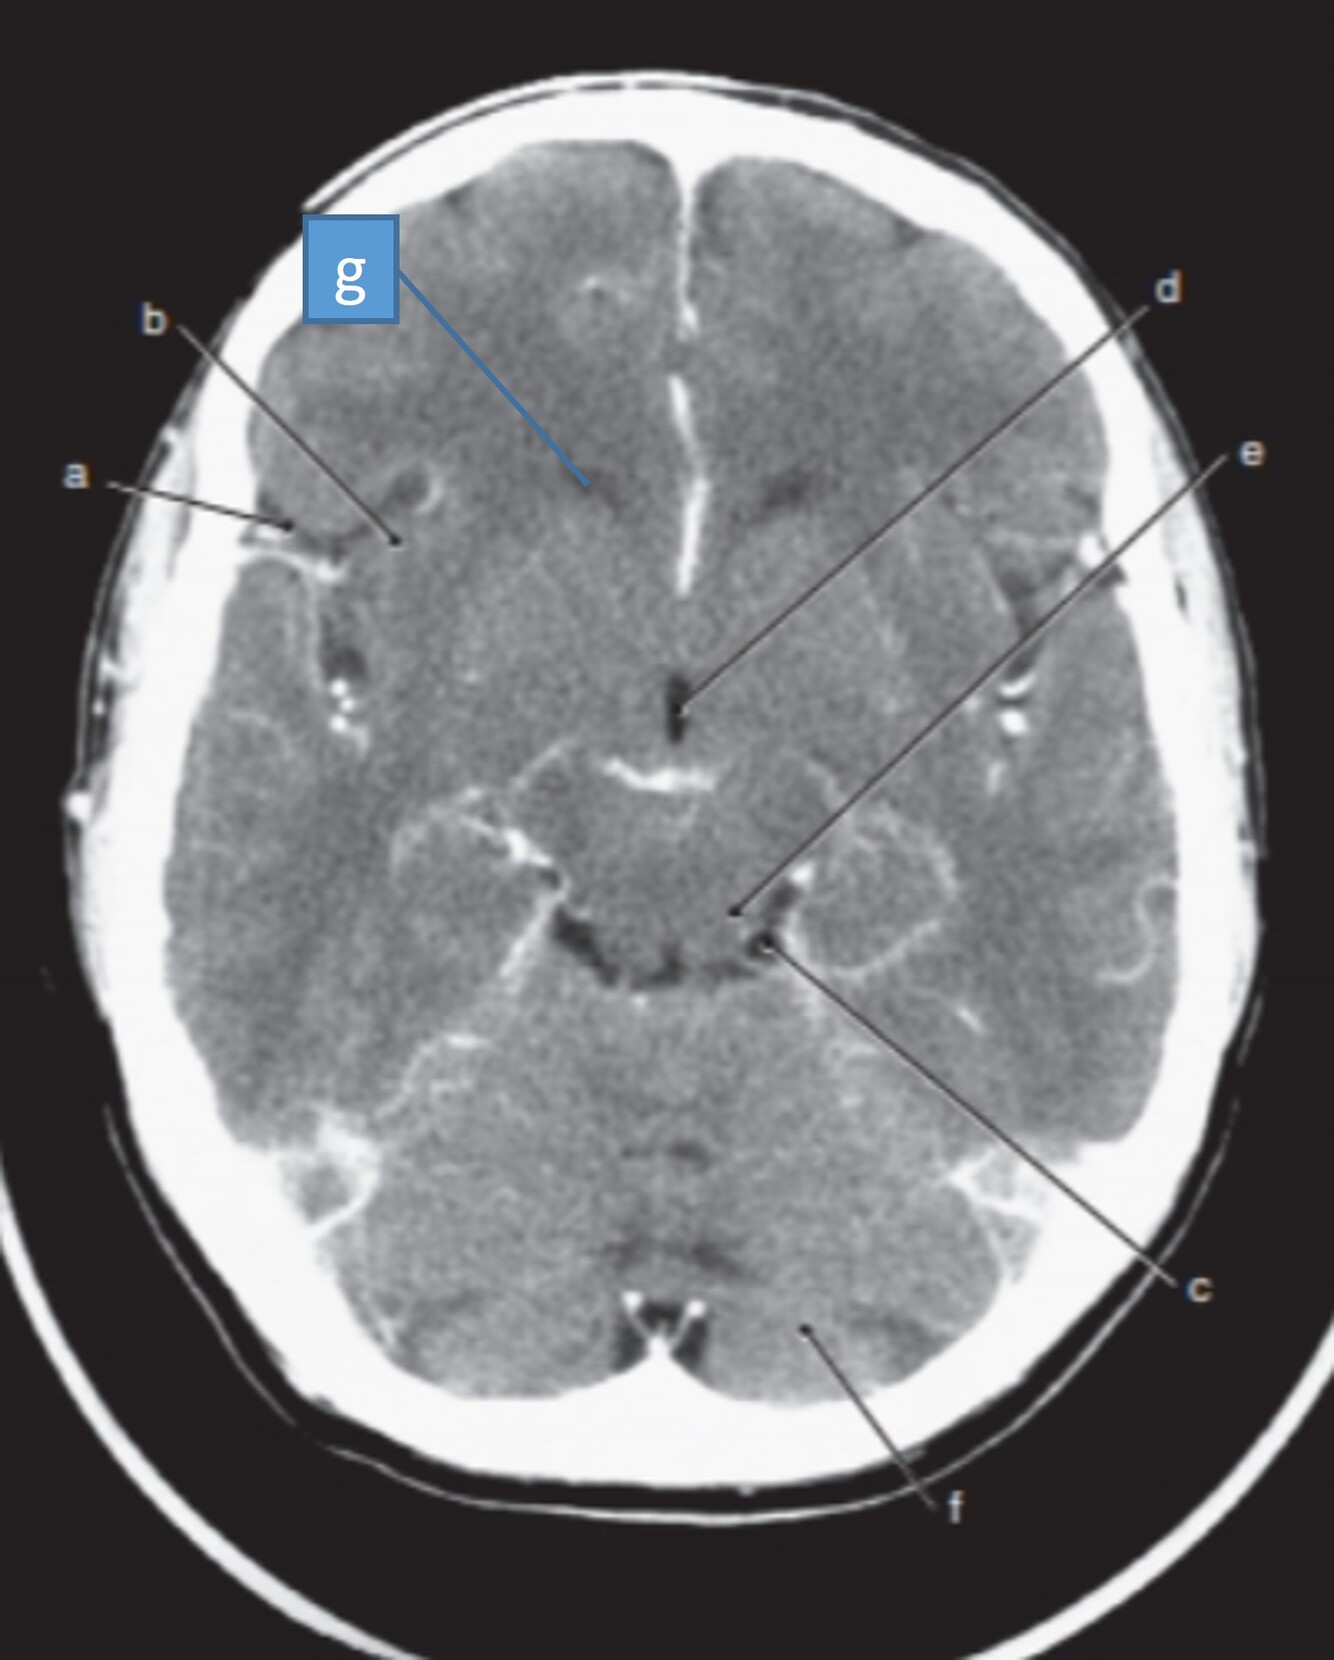

Label 1-6

1=Frontal bone

2-Falx cerebri

3-Left frontal lobe

4-Left anterior cerebral artery

5-Right temporal lobe

6-Temporal horn of left lateral ventricle

Label 7-11

7=Basilar artery

8-Right posterior cerebral artery

9-Internal occipital protuberance

10-Midbrain

11-4th ventricle

Label a,c,d

a=Left cerebral peduncle (of Midbrain)

c=Right ambient cistern (with Rt posterior cerebral artery)

d=Right middle cerebral artery

Label a,b,c,d,f,g

a-Rt lateral fissure

b=Insula

c=Quadrigeminal cistern

d-3rd ventricle

f-Cerebellum

g=Anterior horn (of rt lateral ventricle)